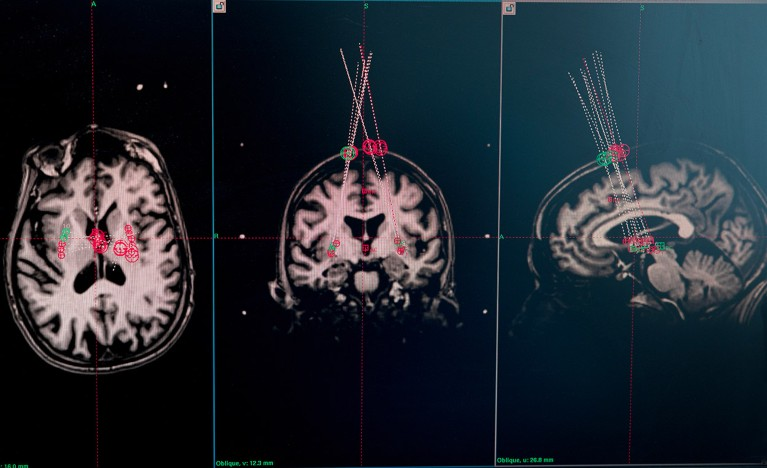

图片

一项试验参与者的脑部磁共振成像扫描被用于规划穿刺针将细胞植入的位置